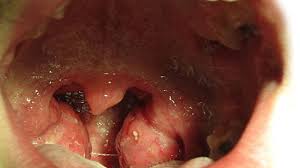

What Does Cancer Sore Throat Feel Like : Cobblestone Throat Pictures Cancer Risk Other Causes Treatment / The most common symptoms are persistent hoarseness, a sore throat lasting longer than four to six weeks, and trouble swallowing.. Early symptoms of throat cancer include hoarseness of the voice, difficulty in normal voice production during speech, changes in the voice, sore throat, continuous dry cough, perceivable pain while swallowing saliva, liquid and solid food, pain in the ear, difficulty breathing, a small swelling or a lump in the throat or neck region, and unexplained weight loss. On the other hand, a lump that occurs without an infection or persists long after an infection resolves may be a sign of throat cancer. Pain while chewing, sores on the neck that don't heal, difficulty swallowing, or hoarseness. The pain of throat cancer will sneak up on you over weeks, and it will lack the symmetry of a regular sore throat. Symptoms of tightness in throat.

Laryngeal Cancer And Early Symptoms Everyday Health from images.everydayhealth.com The most common symptoms which can make you suspect you have throat cancer include difficulty swallowing, a sore throat that doesn't go away, a lump in your neck that is not associated with a recent respiratory infection or persists after an infection is cleared, and weight loss. The pain of throat cancer will sneak up on you over weeks, and it will lack the symmetry of a regular sore throat. Canker sores affect the mucous membrane, the soft protective layer lining the throat and mouth. One may also have difficulty swallowing, and it may be painful to eat or drink. Some even experience a mild burning or itching sensation, which can get worse when swallowing food or water. A canker sore looks like an ulcer, usually with a depression in the center. They may appear slightly sunken, with. Swelling in one or more lymph nodes in the neck is a common symptom of throat cancer, as well as other head and neck cancers.

A canker sore looks like an ulcer, usually with a depression in the center. What does cancer sore throat feel like / what does the start of tonsillitis look like when throat. The middle of the canker sore may appear white, gray, or yellow, and the edges are red. The cause of these mutations is not clear but there are factors that can increase your risk. The hpv vaccine can prevent hpv infection and, therefore, any related cancers.